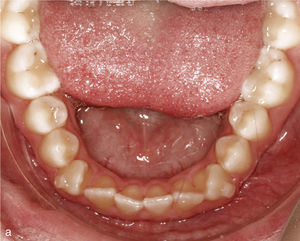

Extracción de dientes anterioresLa falta grave de espacio en el sector anterior hace que en algunos casos sea necesario extraer un diente anterior con el fin de disponer del espacio suficiente para conformar la arcada dentaria y lograr una sobremordida funcional. En la figura 12a se observa la mandíbula de un paciente con falta de espacio en el sector anterior, dientes anteriores rotados y el diente 43 inclinado hacia vestibular. En extracciones realizadas en el sector anteroinferior se colocan sistemáticamente ataches de anclaje en los dientes adyacentes al futuro espacio de extracción. En este caso se colocaron ataches en los dientes 33, 32 y 44, dado que no sólo se cerró el espacio edéntulo, sino que también se realizó una intrusión del sector anteroinferior. La figura 12b muestra el resultado del tratamiento después de la extracción del diente 42 y del cierre del espacio.

Sector anterior de la arcada inferior con dientes rotados y apiñados (a). La conformación de la arcada se realiza mediante la extracción del diente 42 y la colocación de ataches en los dientes 33 a 44. Vista intraoral de la arcada inferior con un aspecto armonioso y el espacio cerrado (b).